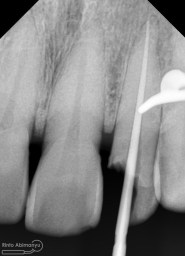

Setelah itu dilakukan pengambilan ronsen kembali…

Alhamdulillah perawatan ini tidak ada kendala dan bisa diselesaikan dalam satu kali kunjungan langsung dua gigi… Ronsen sangat penting dalam prosedur perawatan saluran akar, jadi pesan saya adalah “No Xray, No Endo” 🙂